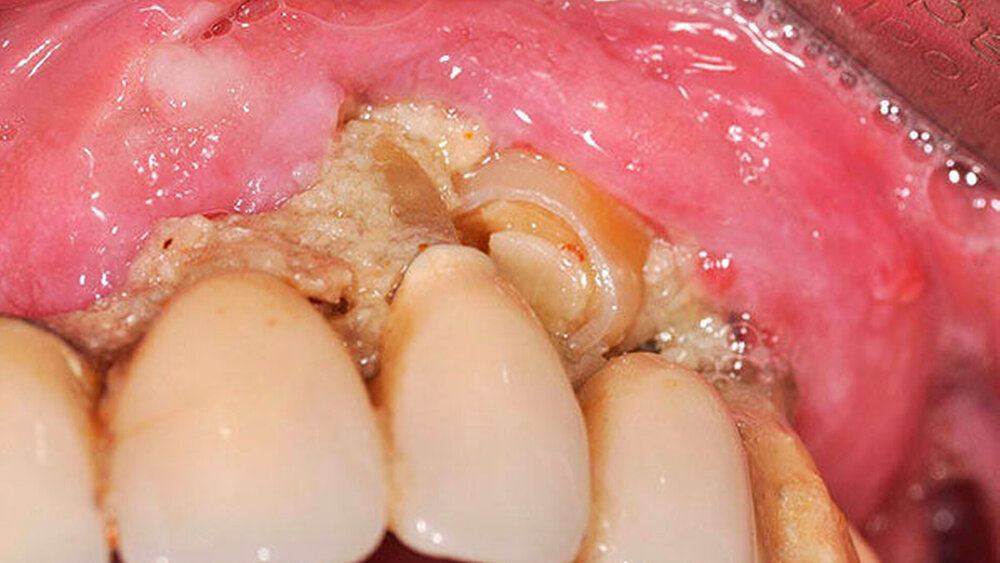

Bei Druckschmerzhaftigkeit im linken Oberkiefer und dort lokalisierter, stark gelockerter Brücke erfolgte die Überweisung des Patienten an die Abteilung für Mund-, Kiefer- und plastische Gesichtschirurgie der Universitätsmedizin Mainz. Klinisch stellte sich der Befund als druckschmerzhafte Strukturveränderung des Hartgewebes unterhalb der maxillär lokalisierten Brücke im rechten Oberkiefer bei drittgradig gelockerter Restbezahnung und insgesamt schlechter Mundhygiene dar (Abbildungen 1 und 2).

In der durchgeführten radiologischen Diagnostik zeigten sich ausgeprägte Parodontopathien mit Verdacht auf eine BRONJ bei gut begrenzter radiologischer Aufhellung mit Kieferhöhlenbeteilung (Abbildungen 3 bis 5). Unter der Verdachtsdiagnose einer BRONJ wurde somit die Indikation zur Zahnsanierung mit Exzision der pathologischen Veränderung im Oberkiefer gestellt. Nach Entfernung der gelockerten Brücke zusammen mit den die Brücke tragenden Zähnen zeigten sich große Mengen harten, anhaftenden Gewebes (Abbildung 6); der unter dem Befund liegende Knochen stellte sich klinisch als vital und ohne Anzeichen einer Nekrose dar.